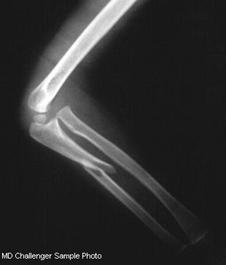

Fractura Galeazzi Fractura Monteggia

Fractura Monteggia Fractura 1/3 proximala radius si ulna Fractura proximala intracapsulara

de humerus